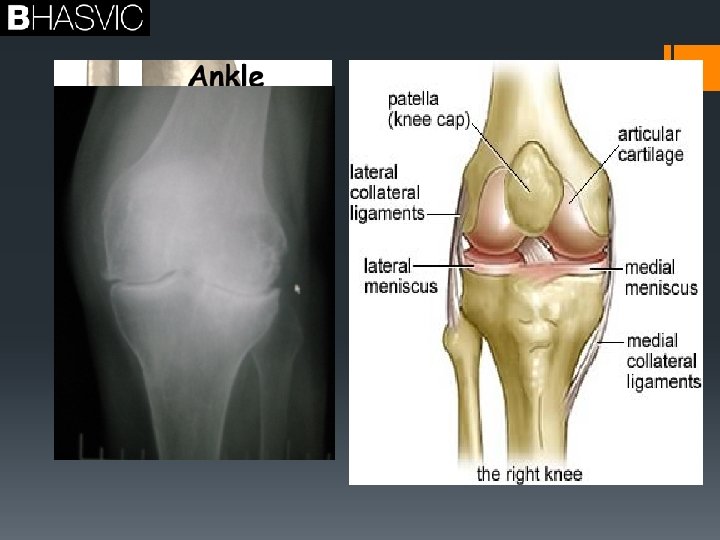

§Joints §Osteoarthritis

Arthritis and Osteoarthritis § § § § Places affected: Hands knees hips spine Cause: unknown Risk factors overweight Joint injury Repetitive strain Problem with alignment Family tendency § Process= Reduction of articular cartilage § Bone spurs § § § § § Control Medication Ice-pack Lifestyle –resting Loosing weight Physical activity/ low impact to increase muscles to support joint Increase strength of tendons Increase strength of ligaments Increase in strength of articular cartilage

Joint stability § Joint stability ; refers to the ability of the surrounding muscle and ligaments to resist movement. § Increase in ligament strength increases the stability. § Is this a good thing for sport? § Can you give a sporting example that will help explain your answer? Answer: Yes Physical activity strengthens ligaments and cartilage, allowing stability when performing eg, golf swing, place kick in football of the supporting leg. A reduction in physical activity will lead to a shortening of ligament reducing flexibility, leaving them prone to injury. Muscle tone is reduced surrounding the joint loosing stability. Can lead to a reduction in synovial fluid and ease of movement.